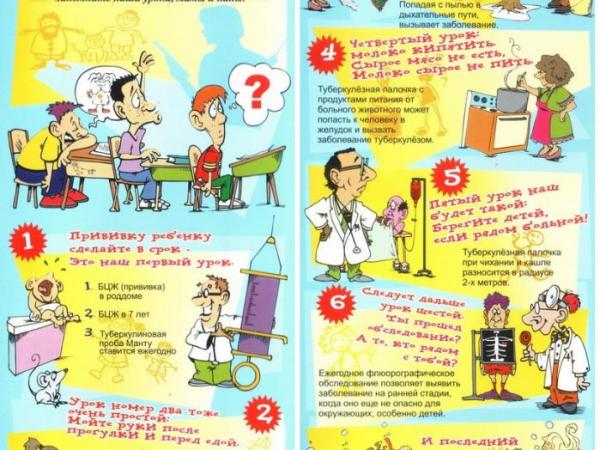

Туберкулез - хроническое инфекционное заболевание, вызываемое микобактериями туберкулеза человеческого или, реже, бычьего вида (последние передаются через молоко и молочные продукты), поражающими в большей мере органы дыхания, а также все органы и системы организма.

Источником инфекции являются больные туберкулезом люди. Наиболее распространенным является воздушный путь заражения. Факторами передачи служат носоглоточная слизь, мокрота и пыль, содержащие бактерии.

Для профилактики туберкулеза очень важно: вести здоровый образ жизни, строго соблюдать санитарно - гигиенические правила:

- мыть руки перед едой,

- не употреблять в пищу немытые овощи и фрукты, а также молочные продукты, не прошедшие санитарный контроль,

Важным моментом для предупреждения туберкулеза является ежегодная постановка пробы Манту, которая дает положительный результат при проникновении патогенных бактерий в организм ребенка